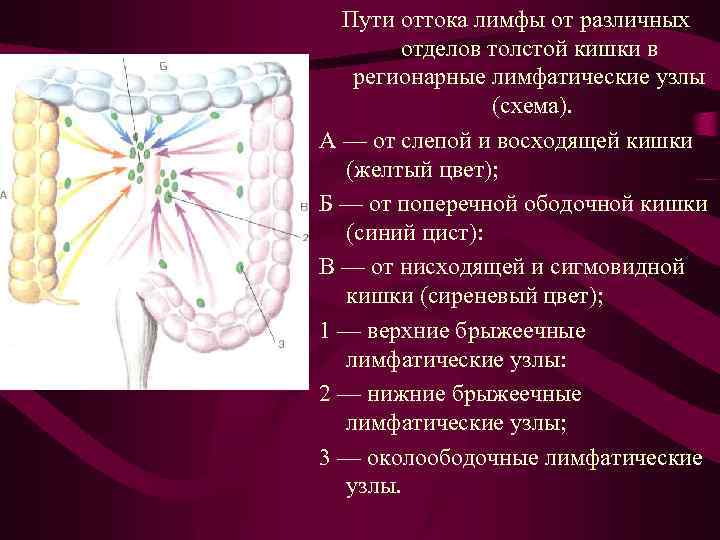

Пути оттока лимфы от различных отделов толстой кишки в регионарные лимфатические узлы (схема). А — от слепой и восходящей кишки (желтый цвет); Б — от поперечной ободочной кишки (синий цист): В — от нисходящей и сигмовидной кишки (сиреневый цвет); 1 — верхние брыжеечные лимфатические узлы: 2 — нижние брыжеечные лимфатические узлы; 3 — околоободочные лимфатические узлы.